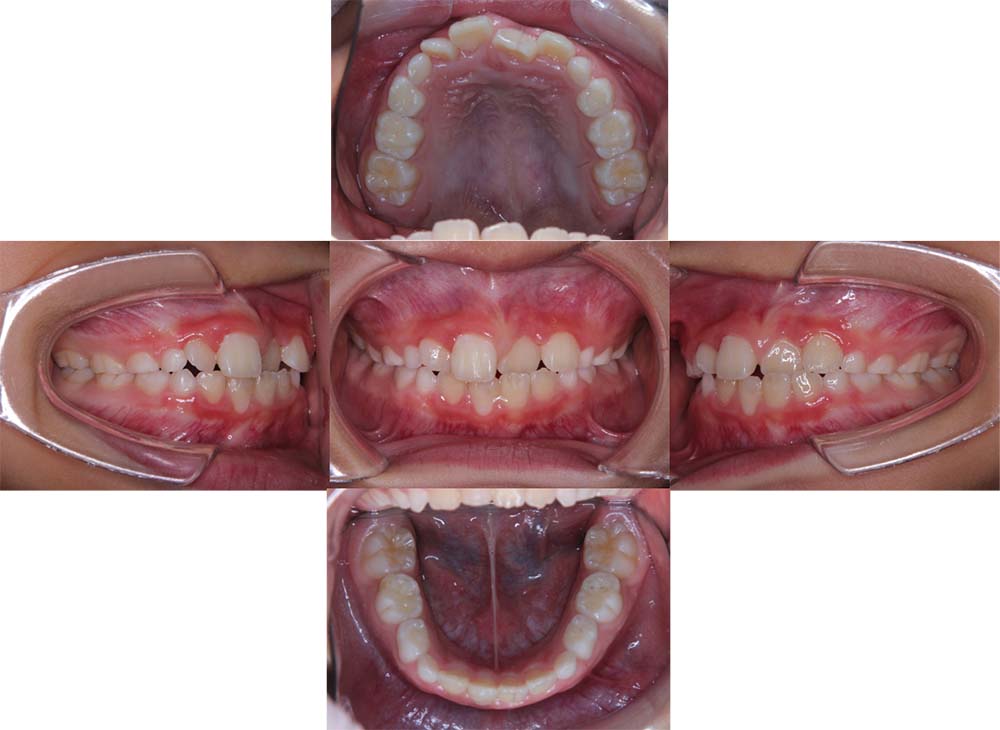

症例01

| 主訴 | 歯並びがガタガタしている。 |

| 診断名あるいは主な症状 | 叢生 |

| 年齢/性別 | 22歳・男性 |

| 矯正ステージ | 大人の矯正治療 |

| 治療方法 | ワイヤー矯正 |

| 抜歯部位/抜歯有無 | 非抜歯 |

| 治療内容 | 上顎大臼歯の遠心移動により前歯のガタガタを排列スペースを獲得し全顎的な排列を行った。 |

| 費用 | 85万円程度(2025.10時点の料金となります。) ※矯正基本料金、審美ブラケットを含む |

| 治療期間 | 2年4ヶ月 |

| 主なリスク・副作用 | 痛み、歯根吸収、歯肉退縮、虫歯、後戻り |